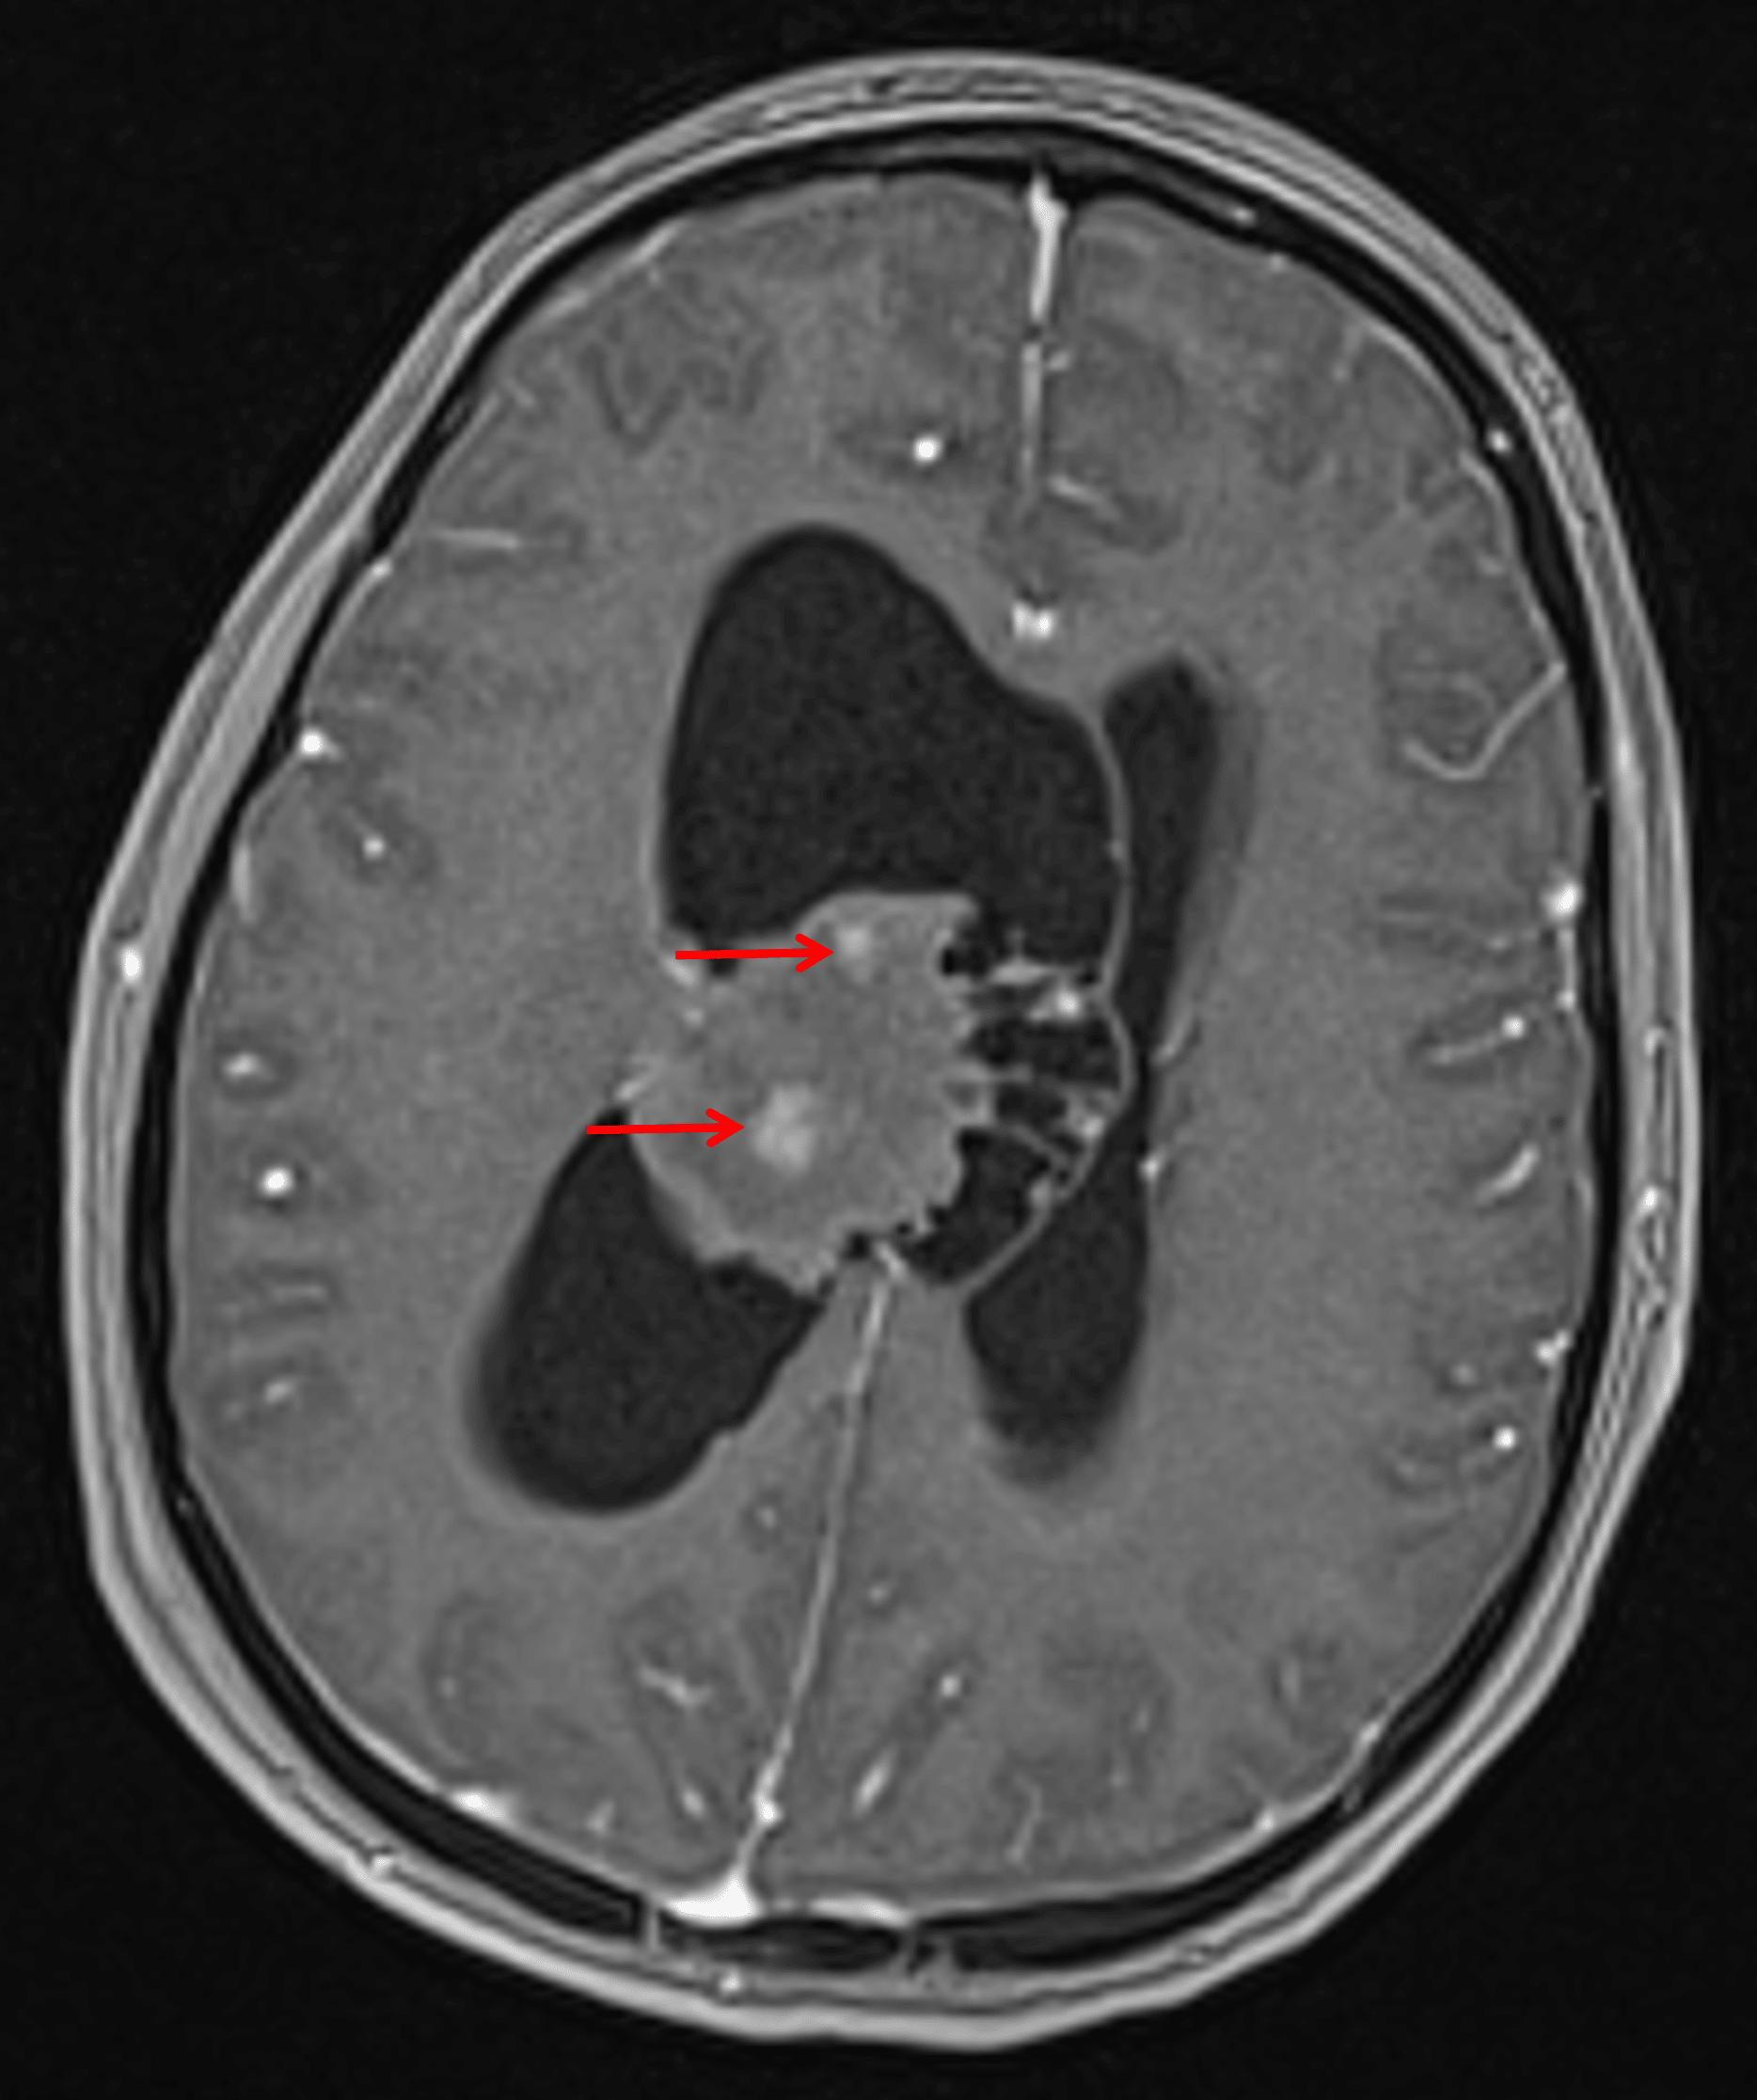

• Patchy internal areas of enhancement

Internal patchy areas of enhancement (red arrows).